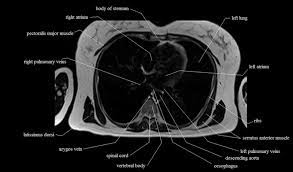

Able to move the upper limb as they originate at the vertebral column and insert onto either the clavicle, scapula or humerus. The chest or thorax is the region between the neck and diaphragm that encloses organs, such as the heart, lungs, esophagus, trachea, and thoracic diaphragm. Posted by radiologypics ⋅ march 21, 2013 ⋅ 1 comment. Superficial back muscles, intermediate back muscles and intrinsic back muscles.the intrinsic muscles are named as such. The muscles of the back can be arranged into 3 categories based on their location: Superficial back muscles, intermediate back muscles and intrinsic back muscles.the intrinsic muscles are named as such because their embryological development begins in the back, oppose to the superficial and intermediate back muscles which develop elsewhere and are therefore classed as extrinsic muscles. Other muscles are small and cover much less space. In the upper back region, the trapezius, rhomboid major, and levator scapulae muscles anchor the scapula and clavicle to the spines of several vertebrae and the occipital bone of the skull. The images are available in the three planes, axial, sagittal. This mri chest (thorax) axial cross sectional anatomy tool is absolutely free to use. Each block is separated by a disc that sits in between and each vertebra has a facet joint on either side. Filed under anatomy, ct, head and neck. All about the back muscles the back anatomy includes the latissimus dorsi, trapezius, erector spinae, rhomboid, and the teres major.

Muscles of the lumbar spine. (2017, elsevier) should be consulted. Related posts of muscles shoulder and back muscle anatomy lower extremity. The erector spinae group is the intermediate layer of the intrinsic muscles of the back. Includes latissimus dorsi, the trapezius, levator scapulae and the rhomboids. The muscles of the back can be arranged into 3 categories based on their location: This mri chest (thorax) axial cross sectional anatomy tool is absolutely free to use. The seventh cervical vertebra, referred to as c7, meets the first of 12 thoracic vertebrae t1 at the base of the neck, a. Lower back pain is a pervasive symptom. Vertebrae_anatomy_ct 2/3 vertebrae anatomy ct epub vertebrae anatomy ct vertebrae anatomy ct bones. Normal radiographic anatomy by dr. The neck consists of seven cervical vertebrae, the building blocks of the spine. Each block is separated by a disc that sits in between and each vertebra has a facet joint on either side.